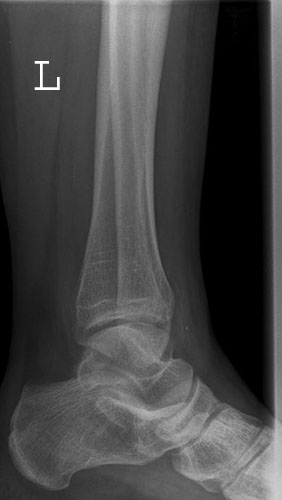

OSG seitlich

Fehler

Doppelkonturierung im vorderen Teil der Talusrolle. Die Fibula ist gegen dem Malleolus internus nach ventral verschoben. Die Längsachse des Talus ist verkürzt. Das untere Sprunggelenk kann nicht beurteilt werden.

Abhilfe

Keilkissen unter den Calcaneus legen bzw. Fuß flacher auf den Zehen auflegen lassen.